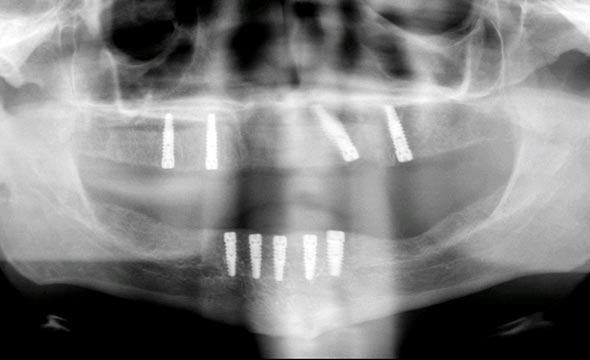

x ray image of dental implants

During a comprehensive periodontal evaluation, your periodontist will thoroughly check the health of the periodontium, the oral soft tissues, jaw bone levels and joint function that support teeth and bite function. He will measure the gums to look for signs of recession, bleeding or infection. Dental xrays are invaluable in this process; they allow the doctor to ‘see’ areas between the teeth and below the gum line that are not visible to the human eye. The xrays will reveal any areas of bone loss, root abscesses or other areas of concern so they can be addressed as early as possible.